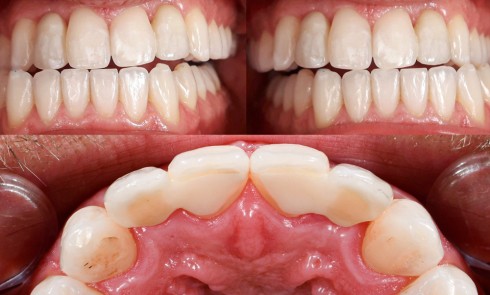

Article réservé à nos abonnés Optimiser le collage des bridges cantilever

Article réservé à nos abonnés Le cantilever céramique : et pourquoi pas l’ailette canine ?

Il y a plus de vingt ans maintenant, ces conceptions ont été révolutionnées par les propriétés améliorées des céramiques, notamment...